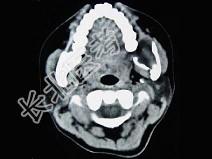

- 单项选择题男,28岁, 无意中发现左下颌骨较对侧隆起,CT如图所示, 最可能的诊断是 ( )

A、下颌骨齿釉细胞瘤

B、下颌骨巨细胞瘤

C、下颌骨角化囊肿

D、下颌骨根端囊肿

E、下颌骨含牙囊肿